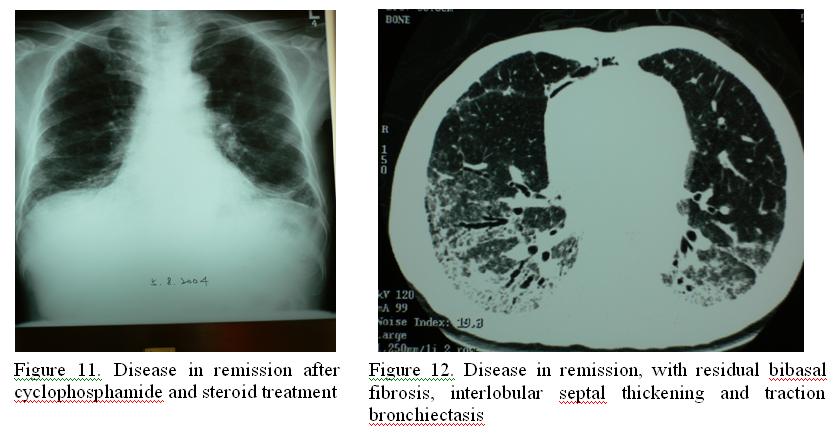

Intravenous methylprednisolone 60mg Q12H and cyclophosphamide was started for second relapse of BOOP/NSIP. Surveillance for CMV pp65 antigenaemia detected 24 pos/ 2×105 WBC upon high dose immunosuppression, although there was no clinical CMV disease. Pre-emptive treatment for CMV reactivation with ganciclovir was given for 3 weeks according to microbiologist recommendation. He improved subsequently and was maintained on cyclophosphamide 50mg daily while methylprednisolone was tapered to 16mg daily upon discharge (Figure 11 & 12).